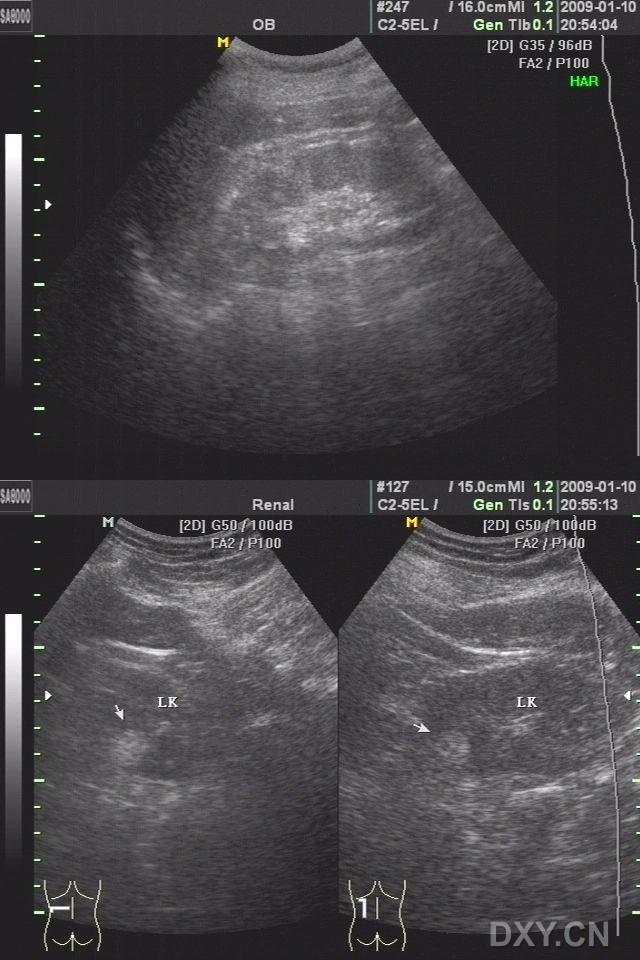

患者,女,67岁,因外伤半天入院查体。既往无不适。查体左肾如图,余(-)。

请战友们按照规定格式发贴,这样无论对错,不仅可以展现自己的思维,同时也可以学习到其它战友的思维方式及模式,这样才能举一反三,提高技艺。下下周在公布CT和CDFI图像。

CT在其内发现脂肪组织成分,考虑为错够瘤可能性大!